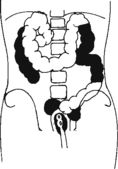

The air-barium distribution within the stomach and large intestine changes with various body positions. By knowing these distribution patterns, one can determine in which body position a radiograph was taken. Air always rises to the highest levels, and the heavy barium settles to the lowest levels (air is black, barium is white).

The fundus is located more posteriorly; therefore in the supine position it would be the lowest portion of the stomach and would be filled with barium.

In both prone and erect positions, the fundus would be filled with air as seen on the drawings below, with a straight air-barium line on the erect.

The ascending and descending portions are located more posteriorly, and thus more of these parts in general would be filled with barium (white) in the supine position and with air (black) in the prone position.

This much separation of barium and air occurs generally only with double-contrast barium-air studies.

Air-fluid levels would be seen in the erect position in which the air would rise to the highest position in each of the various sections of the large intestine, as shown in the accompanying figure.

Right and left decubitus projections (not shown on these drawings) also would demonstrate air-fluid levels, with air again rising to the highest portions.